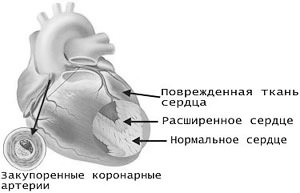

Сердце и сосуды — ишемическая болезнь сердца, атеросклероз, облитерирующий эндоартериит

Сердце являются той мишенью, по которой в первую очередь ударяет курение. Коронарные сосуды, питающие сердечную мышцу, поражаются атеросклерозом, закупориваются холестериновыми отложениями, что приводит к развитию инфаркта миокарда. Курение способствует развитию атеросклероза и в других сосудах организма: закупорка сосудов нижних конечностей у курящих людей нередко приводит к хромоте, зачастую становится показанием к ампутации ног.